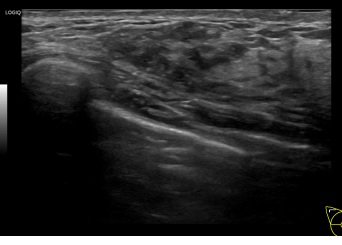

상기환자는 외부검사이상소견으로 내원하신 40대초반

여성분으로 의심스러운 우측혹 조직검사 시행해 유방암으로 진단되었습니다